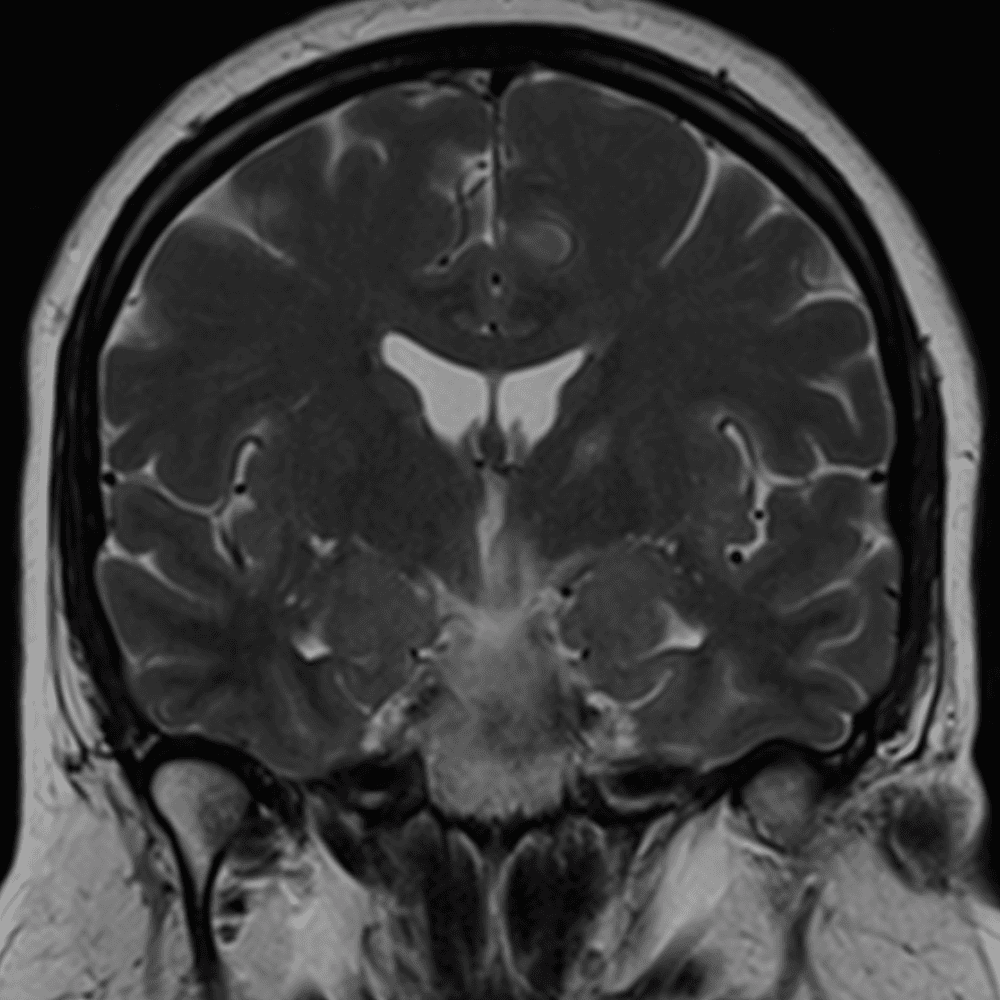

๋ฏธ๋ฌ˜ํ•˜๊ฑฐ๋‚˜ ์–ด๋ ค์šด ์‚ฌ๋ก€์™€ ์ผ๋ถ€ ์ •์ƒ ์‚ฌ๋ก€๋ฅผ ํฌํ•จํ•˜์—ฌ ๋‹น์ง์„ ์‹œ๋ฎฌ๋ ˆ์ด์…˜ํ•ฉ๋‹ˆ๋‹ค.

50 ์‚ฌ๋ก€